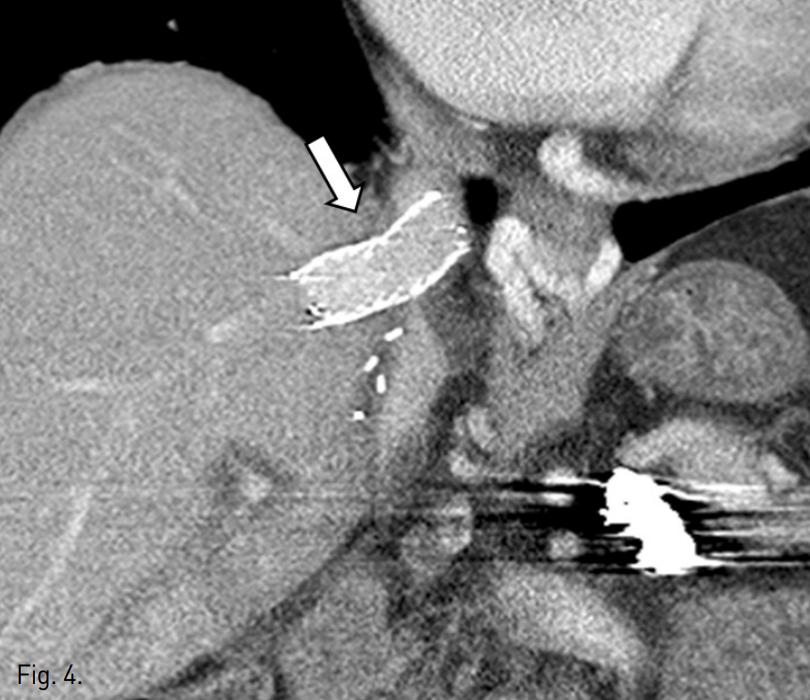

수술 후 1일 째 시행한 color doppler 검사에서 오른간 정맥의 spectral waveform이 monophasic하여 hepatic outflow의 장애가 의심되었다. Liver CT에서 오른간정맥의 기시부가 좁아져 있었으며(Fig. 1) 인접한 아래대정맥 내에 소량의 혈전이 의심되었다. 정맥조영술을 시행하였으며 오른간정맥과 아래대정맥 사이의 관강내(intraluminal) 협착 소견을 확인할 수 있었다(Fig. 2).

Fig. 1

Contrast-enhanced CT scan shows a focal stenosis at right hepatic vein-IVC anastomosis (arrow).